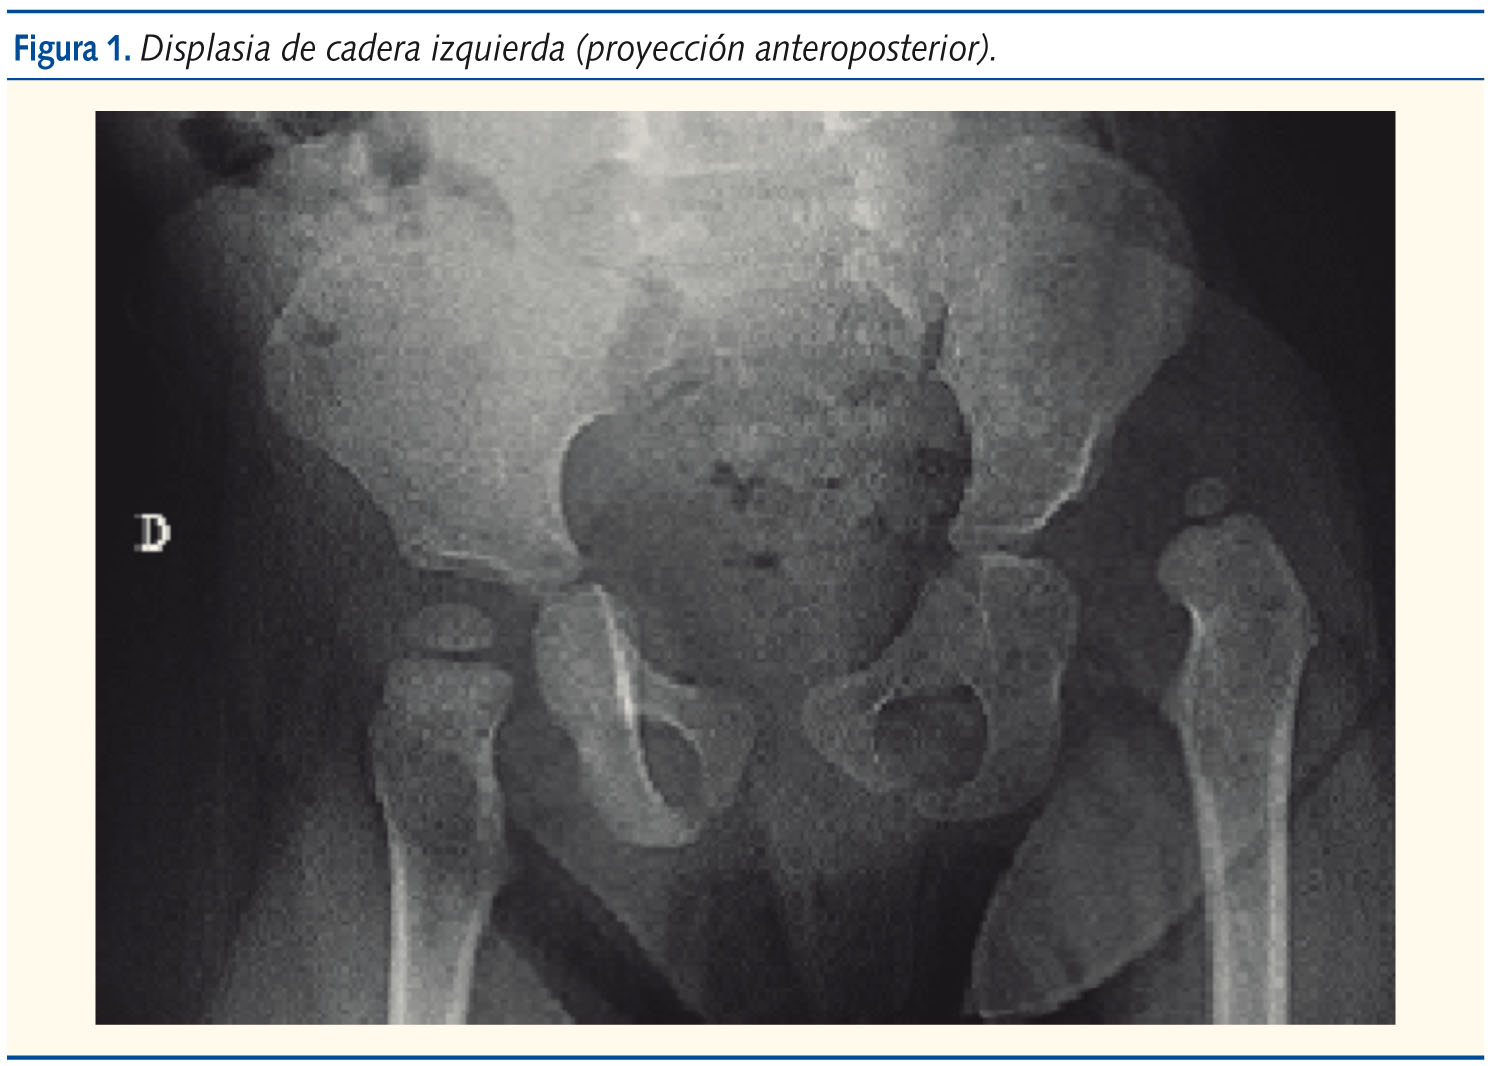

La exploración revelaba una niña de aspecto saludable, bien nutrida, sonriente. Los hallazgos anormales se limitaban al examen ortopédico: asimetría de pliegues inguinales y glúteos, acortamiento del miembro inferior izquierdo de 1,5 cm, discreta limitación a la abducción de cadera izquierda, no dolorosa, e hiperlordosis lumbar. A su vez, destacó un patrón de marcha anormal, oscilante, “de pato”, de Trendelemburg. La radiografía de pelvis mostró un acetábulo displásico y cadera izquierda luxada (figuras 1 y 2).